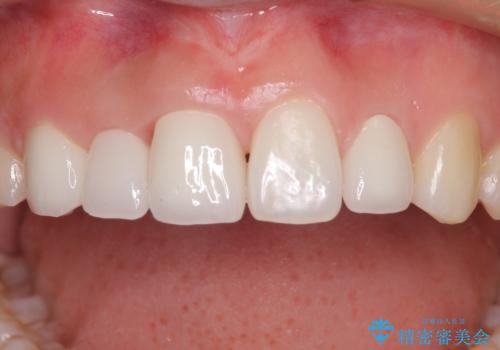

欠損歯と矮小歯 矯正治療と前歯のセラミック治療

- 前歯の隙間を気にして来院された患者様です。

診察の結果、前歯が1本欠損しており、さらに矮小歯(通常よりも小さい歯)が1本存在していました。

矯正治療後には欠損部はオールセラミックブリッジに、矮小歯はオールセラミッククラウンにて補綴することとしました。